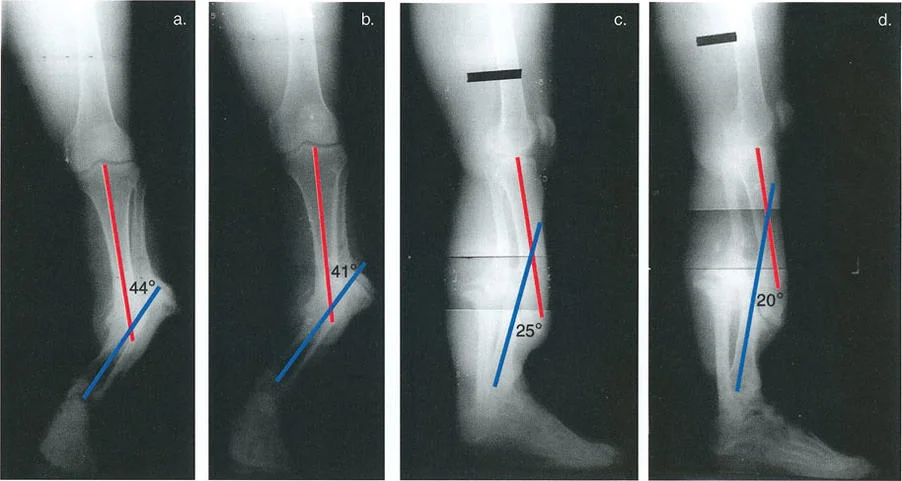

- الأشعة السينية الأمامية الخلفية والجانبية (AP and Lateral Radiographs): تُستخدم لتقييم التشوه في المستويين التاجي (التقوس للداخل أو الخارج) والسهمي (التقوس للأمام أو الخلف).

الشكل 12-29أ، ب: الاختلافات في القياسات الإسقاطية الناتجة عن منظورين مرجعيين مختلفين (المتطابقات المنظرية). في المنظر الأمامي الخلفي بالنسبة للقطعة المرجعية الأمامية للركبة، تبدو الساق بـ 4.75 درجة من التقوس للداخل. أما بالنسبة للقطعة المرجعية الأمامية للقدم، فتبدو بـ 5.5 درجة من التقوس للخارج. تختلف قياسات الدوران أيضًا بناءً على منظور المراقب.